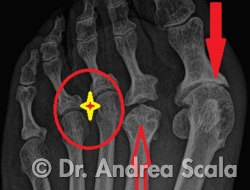

La radiografia dell’avampiede non può mostrare il neuroma, ma in alcuni casi, può spiegare come una anomalia del piede può causare il Neuroma di Morton. La radiografia mostra che la paziente è stata operata: l’alluce valgo (freccia rossa) è ritornato, ma purtroppo è anche rigido per l’artrosi. Il 2° dito e il 2° metatarso sono stati compromessi dall’intervento e non funzionano (freccia rossa). Tutto il peso è sopportato dal 3° e 4° metatarso, esattamente dove la paziente soffre per il Neuroma di Morton (cerchio rosso). La foto dell’intervento mostra il nervo plantare ingrossato dalla infiammazione (“neuroma”).